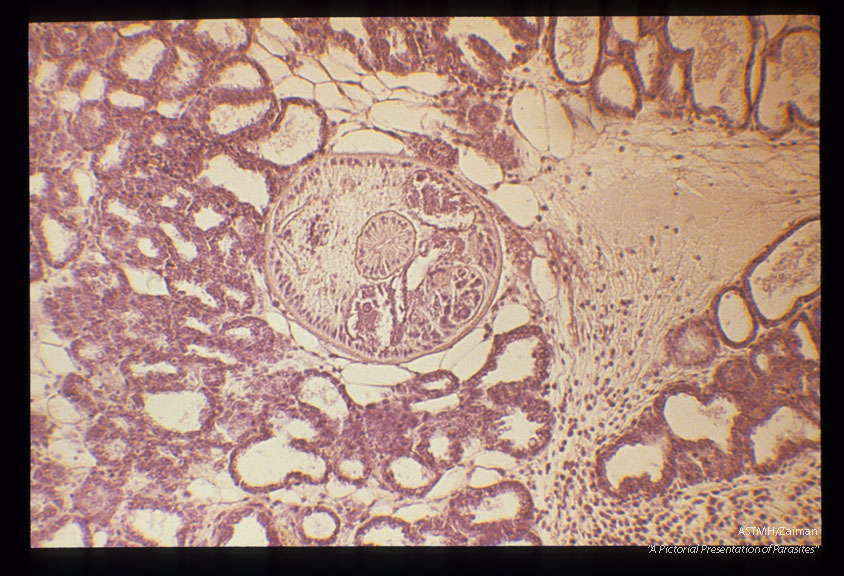

Mesocercarial stage in the adipose tissue of a mouse mammary gland. Note the large, unicellular penetration glands. Low and high magnifications.

Alaria marcianae

Description: Mesocercarial stage in the adipose tissue of a mouse mammary gland. Note the large, unicellular penetration glands. Low and high magnifications.